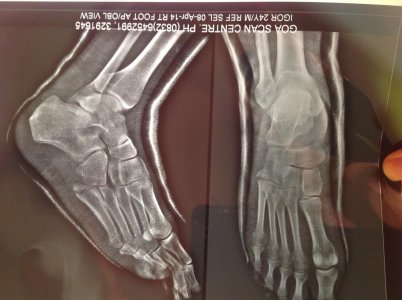

Здравствуйте! Я нахожусь сейчас за границей, в Индии. 28 марта упал с байка и перелом 5-й плюсневой кости. Снимок сделал в этот же день, нога была опухшая и 5 дней я ходил в повязке, 2 апреля мне наложили гипс и сказали носить его три недели, на ногу можно будет чуть-чуть наступать спустя неделю. После снятия гипса, два-три дня продолжать ходить на костылях, потом можно просто начинать полноценно ходить.

Спустя 11 дней после падения сделал повторный снимок когда уже был в гипсе.

Хотел спросить у Вас, все ли верно сказал доктор?

Вложения

• image.jpg

image.jpg

174,5 КБ · Просмотры: 1 127

223,6 КБ · Просмотры: 828

При данном переломе гипсовая иммобилизация должна составлять 4-5 недель.